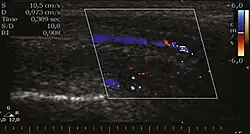

Venous drainage is performed by the deep and superficial dorsal veins of the penis. The dorsal arteries of the penis are located adjacent to the deep dorsal vein and a cavernous artery is located in the center of each corpus cavernosum. On color Doppler, the cavernous arteries present single phase flow. In the flaccid penis (Figure 3), the normal cavernous arteries show a systolic peak between 11 and 20 cm/s. At the beginning of erection, the systolic and diastolic flows undergo progressive increases. When vein occlusion begins, the diastolic flow decreases progressively, and once stiffness is established, it becomes negative.[1]